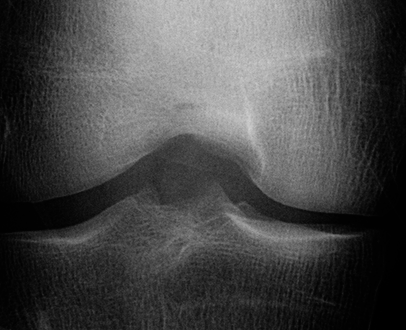

Knee OA develops gradually over years and progresses in stages. In general, the severity of knee OA is divided into five stages. The first stage (stage 0) corresponds to normal healthy knee and the final stage (stage 4) corresponds to the most severe condition (see Figure 2). The most commonly used systems for grading knee OA are the International Knee Documentation Committee (IKDC) system, the Ahlback system, and the Kellgren & Lawrence (KL) grading system. The other widely used non-radiographic knee OA assessment system is WOMAC666Western Ontario and McMaster Universities Osteoarthritis Index, which measures pain, stiffness, and functional limitation. The public datasets, the OAI and the MOST used in this work, are provided with the KL grades and they are used as the ground truth to classify the knee OA X-ray images.

Refer to caption

Figure 2: The Kellgren and Lawrence grading system to assess the severity of knee OA.

The KL grading scale was approved by the World Health Organisation as the reference standard for cross-sectional and longitudinal epidemiologic studies [7, 22, 24, 25]. The KL grading system is still considered the gold standard for initial assessment of knee osteoarthritis severity in radiographs [1, 5, 6, 7]. Figure 2 shows the KL grading system. The KL grading system categorizes knee OA severity into five grades (grade 0 to 4). The KL grading scheme for quantifying knee OA severity from X-ray images is defined as follows [1, 5]:

• Grade 0 : absence of radiographic features (cartilage loss or osteophytes) of OA.

• Grade 1 : doubtful joint space narrowing (JSN), osteophytes sprouting, bone marrow oedema (BME), and sub-chondral cyst.

• Grade 2 : visible osteophytes formation and reduction in joint space width on the antero-posterior weight-bearing radiograph with BME and sub-chondral cyst.

• Grade 3 : multiple osteophytes, definite JSN, sclerosis, possible bone deformity.

• Grade 4 : large osteophytes, marked JSN, severe sclerosis, and definite bone deformity.